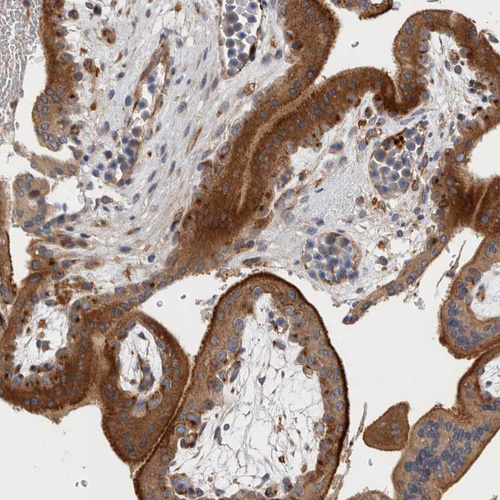

Immunohistochemical staining of human lymph node shows strong cytoplasmic positivity in non-germinal center cells.